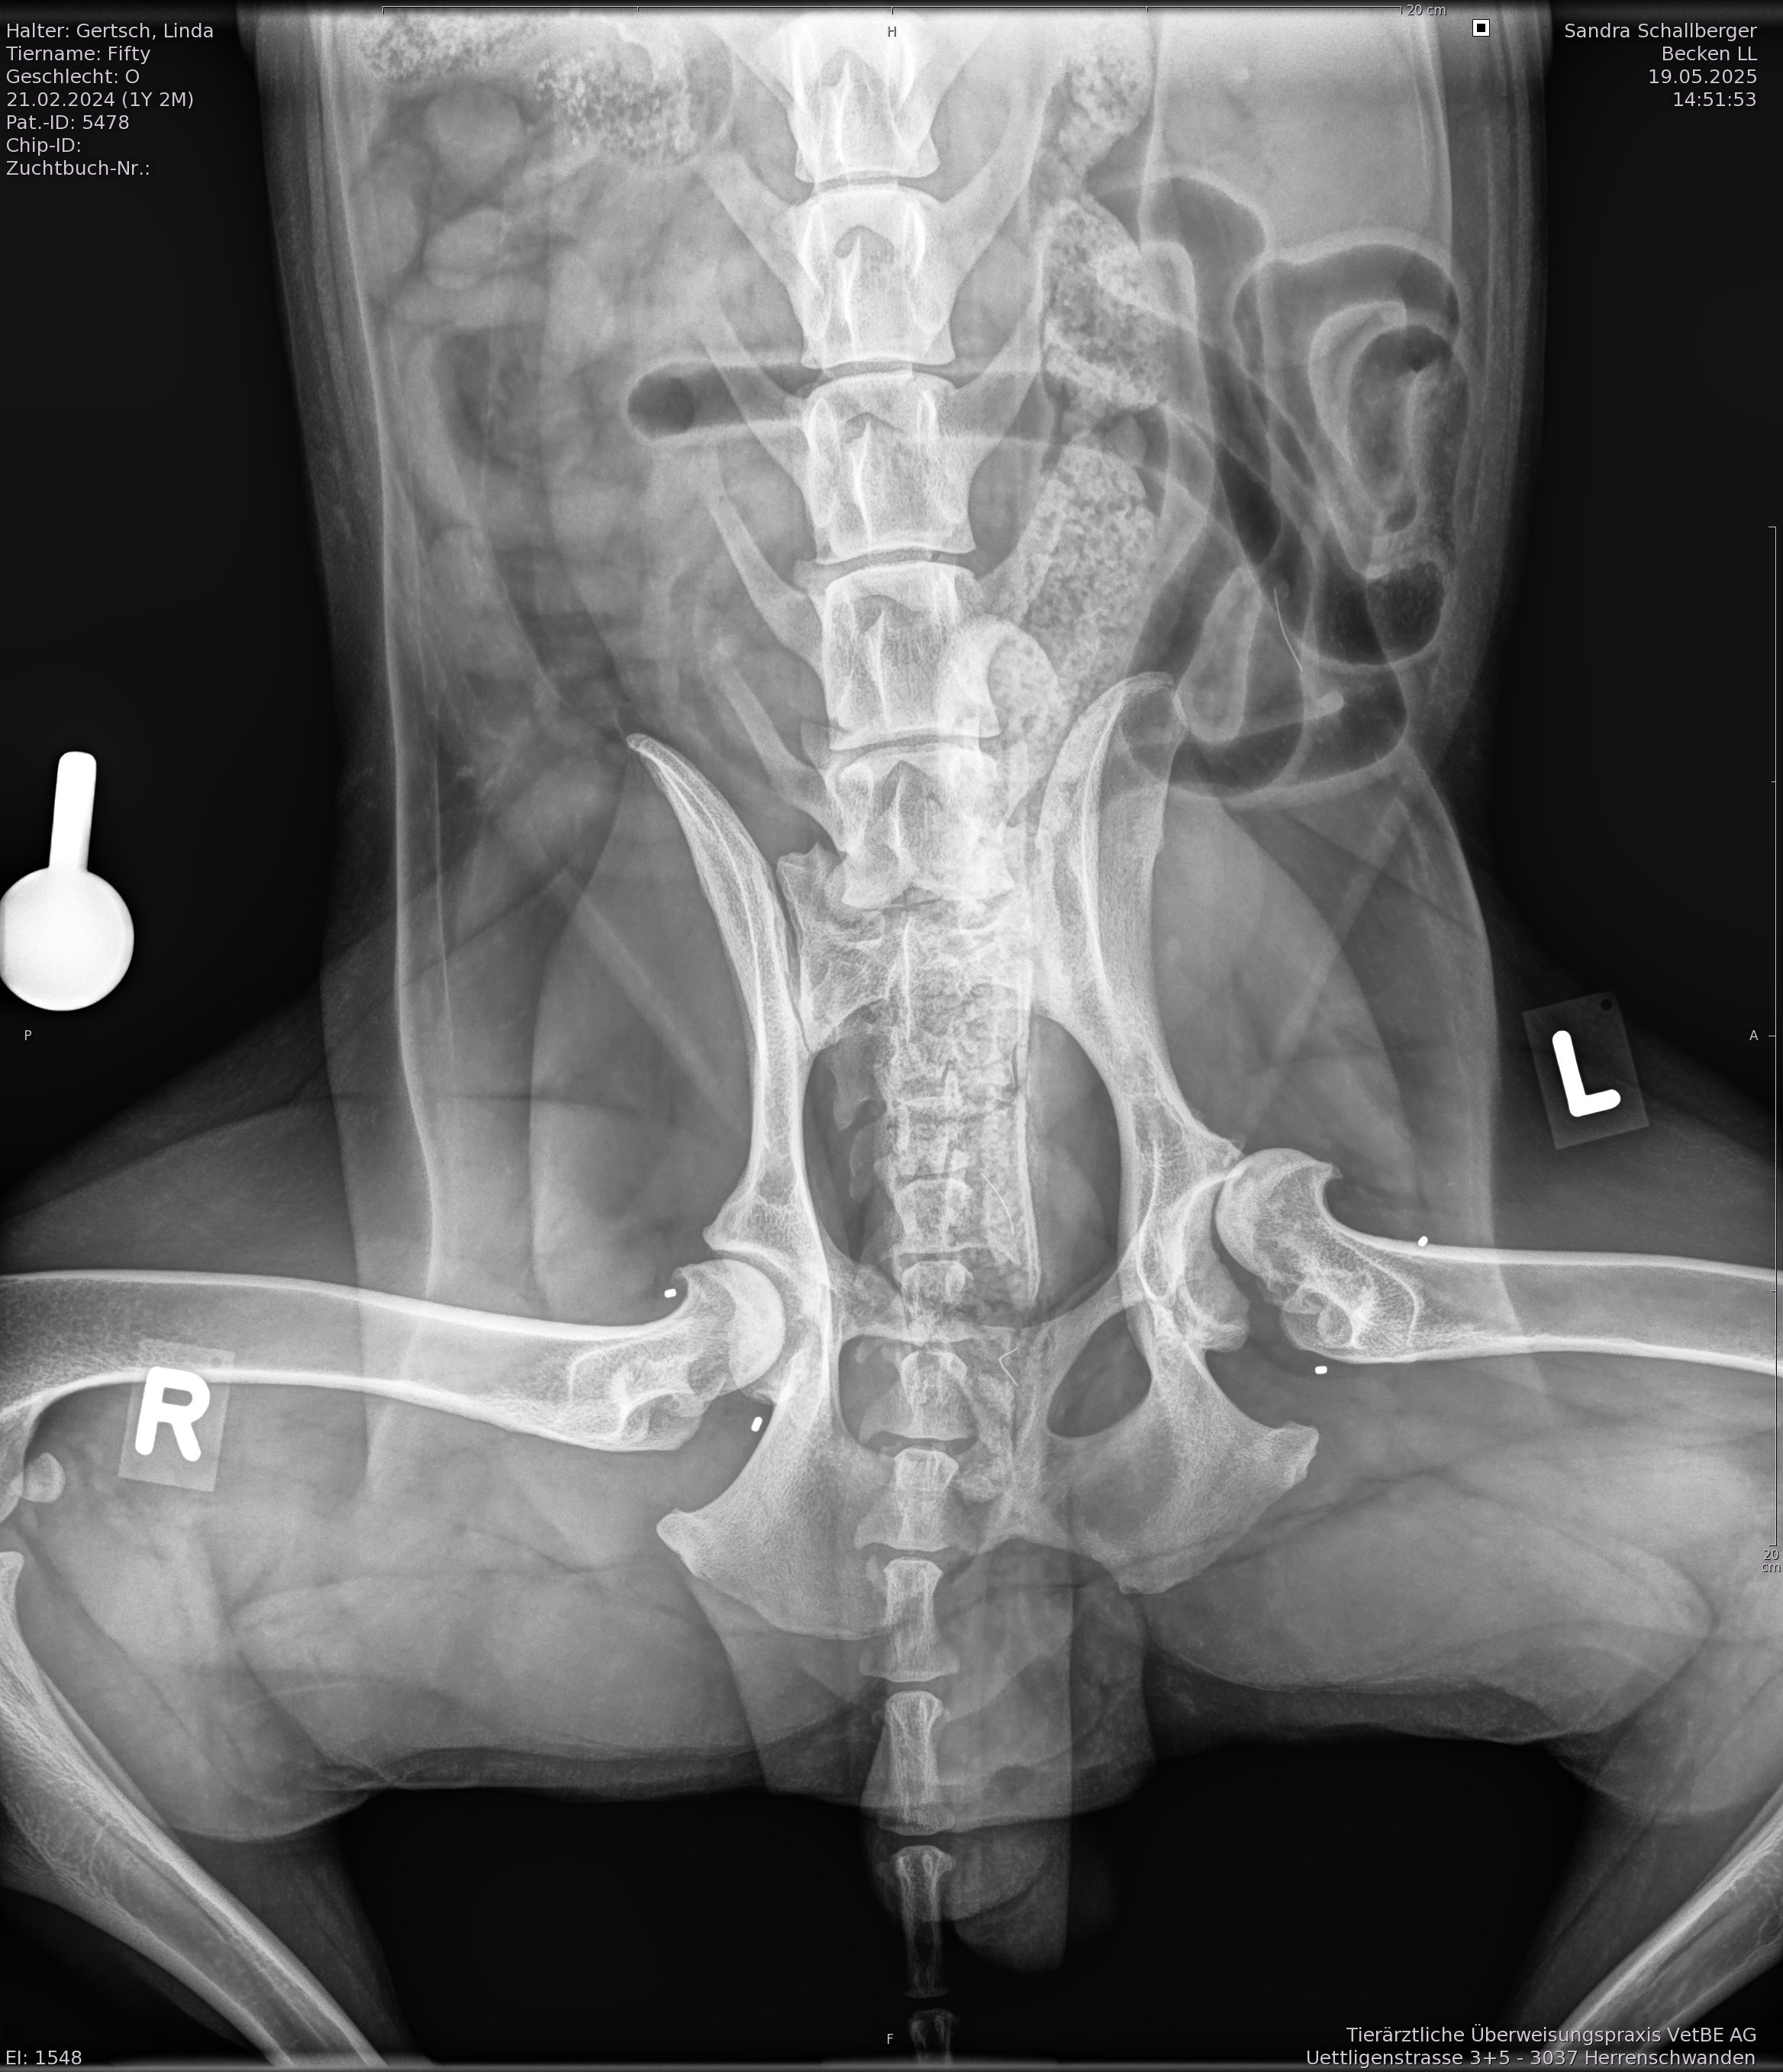

- Schwere Hüftdisplasie auf beiden Seiten

Im Januar 25, als Fifty 11 Monate alt war, wurde die Diagnose gestellt. Eine schwere Hüftdisplasie auf beiden Seiten (Arthrose da).

Das hochgeladene Bild zeigt den aktuellen Zustand (Mai25).

Sein Zustand verschlechterte sich trotz allen möglichen Therapien rasant und nach einem erneuten Röngten im Mai, gab es nur eine Möglichkeit: Hüftprothese für die linke Seite.